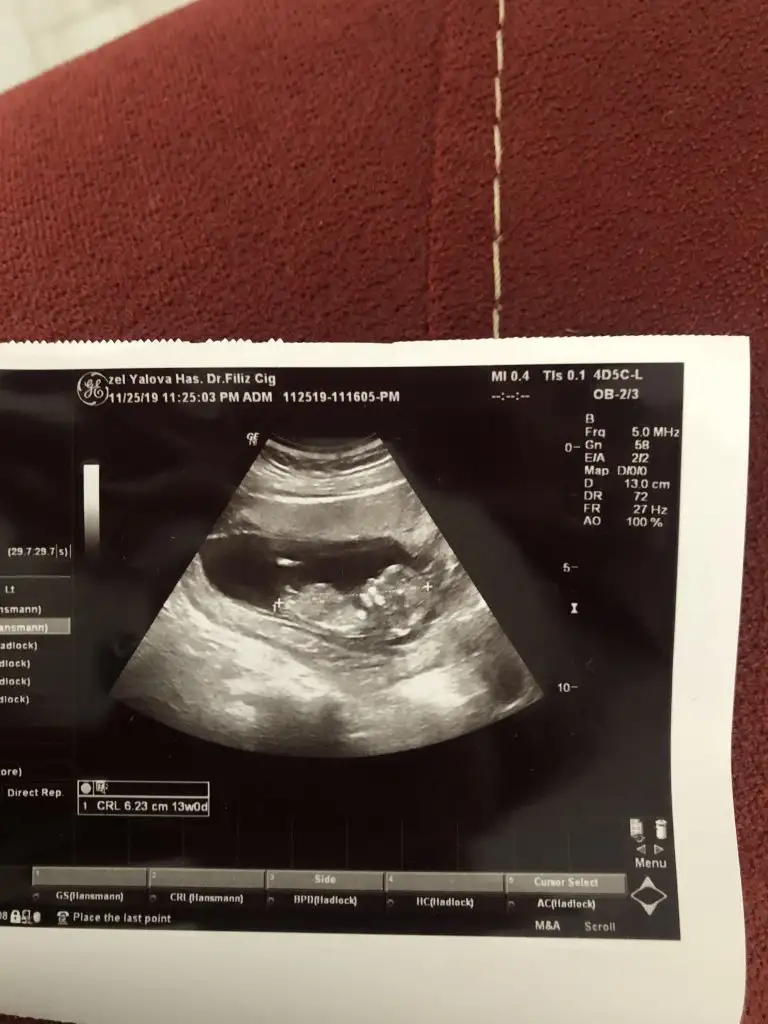

dr soylemeden siz gorun genital nub teorisi ( bebegin cinsiyeti)

Bana da bakar mısınız 🙂

Bunlar 12 hafta usg sizce nedir cinsiyet ikra hanımmm çok heycanlıyım doktor bişey söylemedi 😌